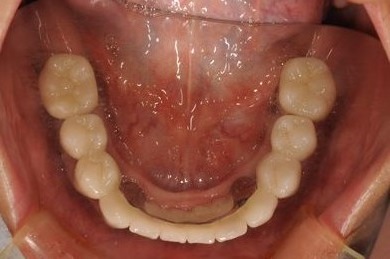

骨再生スピードインプラント治療+セラミック治療

| 治療内容 | インプラント9本(抜歯即日スピードインプラント、ソケットリフト、テンポラリーインプラント+仮歯)、メタルボンドセラミッククラウン18本、メタルボンドセラミックブリッジ6本(メタルボンド用土台6本)、遊離歯肉移植術 | ||||||||||||||||||||||||||||||||

| 治療期間 | 1年8ヶ月 |